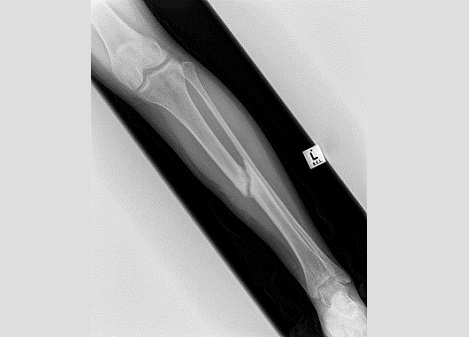

Fig9. - Tibia fracture non-union.

Fig9. - Treated with a hexapod type external fixator.